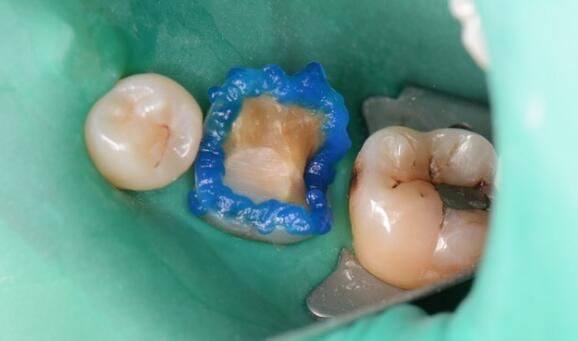

36牙中龋 36牙嵌体修复

术后形态恢复好,患者满意。